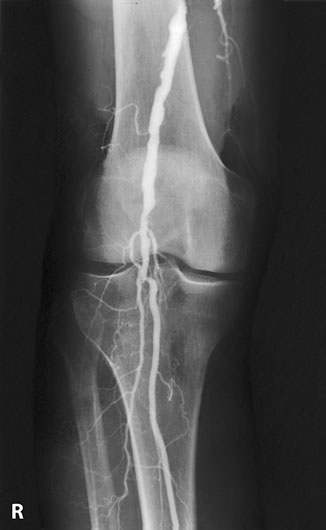

The most favourite subspecialty was angiography and interventional work particularly in the vascular field. This was the first angioplasty performed in the department. This represents atheroma with a focal stricture of the left femoral artery which was dilated with the presented result. Note that the atheromatous process is not limited to one area.

Femoral artery stricture post dilatation. Note the ragged appearance of the dilated atheromatous plaque.